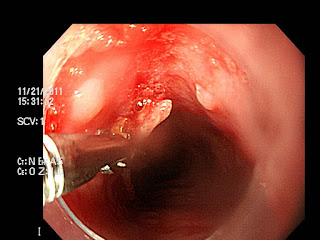

| 식도에 박혀있는 생선가시, 식도는 궤양이 관찰된다. |

| 내시경으로 제거중. |

| 제거 후, 하얀 궤양이 보인다. |

| 길이는 2cm 정도 이고 끝이 상당히 날카롭다. |